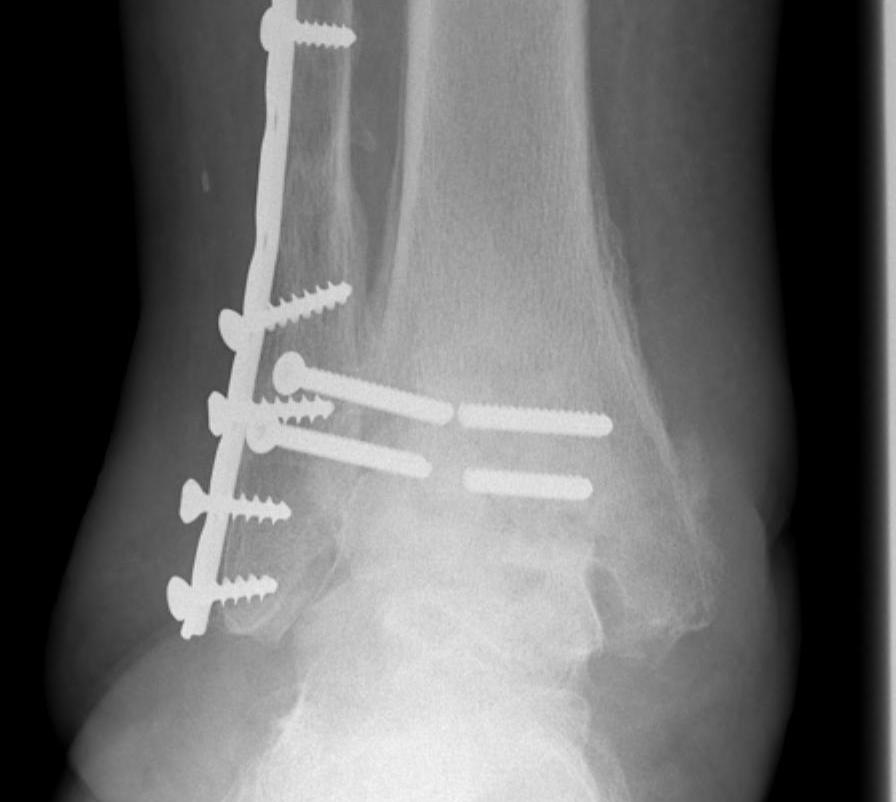

Operative Management

Diabetes / elderly / fragility fractures

Issues

High risk infection / wound complications / loss of fixation

Timing of surgery

Operate when swelling reduced / wrinkling / resolution of blisters

- risk not being able to close wounds / infection

- higher risk with bimalleolar / 2 incision operations